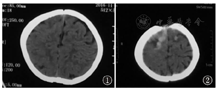

患儿,女,1岁,因"发热3 d,抽搐2次"入院。患儿3 d前出现发热,体温最高39.4 ℃,抽搐2次,抽搐时双眼上翻,四肢强直抖动,意识不清,口唇发绀,口吐白沫,第1次约1 h,第2次约15 min,抽后如常,伴轻咳,无喘息,无呕吐、腹泻,无皮疹,无鼻衄等。既往体健。2个月会抬头,4个月会翻身,7个月能坐,并萌牙,现能叫爸爸妈妈,可扶走。无药物及食物过敏史。按时接种疫苗。查体:体温37 ℃,神志清楚,反应可,球结膜无水肿,咽充血,呼吸24次/min,双肺呼吸音粗,未闻及干湿性啰音,心率110次/min,心音有力,律齐,未闻及杂音,腹软,肠鸣音正常,四肢肌力、肌张力正常,布氏征、克氏征、双侧巴氏征阴性。入院后患儿仍发热,体温波动于36.2~38.4 ℃,第3天患儿出现呕吐,呈喷射性,嗜睡,左上肢肌力下降,未抽搐。入院查血白细胞计数7.30×109/L,血红蛋白110 g/L,血小板计数254×109/L,C反应蛋白1.68 mg/L,异型淋巴细胞0.04。肝功能、心肌酶谱、血糖、血氨、血乳酸均正常。淋巴细胞亚群及免疫球蛋白检测正常。入院第8天脑脊液生化、常规、降钙素原正常。脑脊液涂片、墨汁染色阴性。脑脊液EB病毒、结核分枝杆菌、肺炎支原体、单纯疱疹病毒Ⅰ型均阴性。血培养及脑脊液培养阴性。脑脊液免疫性脑炎相关抗体(NMDA-R-A、CASPR2-Ab、AMPA1-R-Ab、AMPA2-R-Ab、LGI1-Ab、GABAB-R-Ab均阴性)、寡克隆区带检测阴性[脑脊液免疫球蛋白G 23.1 mg/L(正常范围10~40 mg/L)、血清免疫球蛋白G 5.54 g/L(正常范围7~17 g/L)、脑脊液IgG寡克隆区带阴性、血清IgG寡克隆区带阴性、脑脊液特异性IgG寡克隆区带阴性]。脑电图检查正常。入院前1 d头颅CT:平扫未见明显异常(图1)。入院第3天头颅CT示脑灰白质分界欠清,双侧额顶叶多发高密度影,伴周围水肿,双侧额顶叶缺血改变,左侧额顶叶脑沟增宽(图2)。入院第4天头颅磁共振成像(MRI)示双侧背侧丘脑形态信号异常,脱髓鞘改变,双侧大脑半球白质多发出血灶,并少许强化及周围水肿,考虑急性坏死性出血性白质脑炎可能,垂体强化欠均匀,Rathke囊残留?颅脑MRA扫描未见明显异常(图3)。入院第10天复查头颅MRI+脊髓MRI:颅内多发异常信号影,考虑出血性改变(亚急性中期),病变水肿范围较前增大,出血病变增多(图4),脊髓MRI未见异常。脑静脉核磁血管成像:窦汇形态异常,考虑先天变异。入院后诊断颅内多发病变性质待查:AHLE?惊厥持续状态,支气管炎。给予利巴韦林、头孢噻肟抗感染,止血,降颅压,地塞米松等治疗,患儿体温正常,无呕吐,无抽搐,无嗜睡,左上肢肌力逐渐恢复,临床症状缓解,生长发育同同龄健康儿童,但复查头颅MRI好转不明显,家长要求出院,院外随访2个月病情未进展,患儿无抽搐,可独走。

脑脊液检查示颅内压升高,细胞数增加或正常,糖和氯化物正常。该患儿脑脊液检查未见异常。患者早期CT可正常,也可显示广泛的脑组织水肿及白质内低密度灶,可夹杂点状高密度影。MRI的T1加权像表现为广泛的脑组织水肿,单侧或双侧后额部、颞叶或顶叶白质的多发低密度灶,部分病灶可融合成片,从脑室周围延伸至皮质下白质及灰白质交界处,可有明显占位效应[2,3]。MRI的T2加权像和液体衰减反转恢复相对本病更敏感,可见双侧多灶性白质高信号,广泛高信号白质水肿内有多发的斑点状低信号,提示不同阶段的出血[5]。轻症患者脑组织活检实施困难时,可通过头颅影像学检查,做出早期诊断,做出积极治疗,对于改善患者预后有很大帮助。该患儿早期行头颅MRI及CT检查,经积极给予脱水降颅压、激素等治疗后,临床症状改善,复查头颅MRI未见明显改善,考虑可能与影像学检查滞后有关。